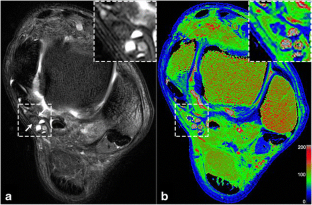

• Tibial nerves in patients with DPN showed T2 hyperintensity and enlargement.

Wang D, Zhang X, Lu L et al (2015) Assessment of diabetic peripheral neuropathy in streptozotocin-induced diabetic rats with magnetic resonance imaging. Eur Radiol 25:463–471